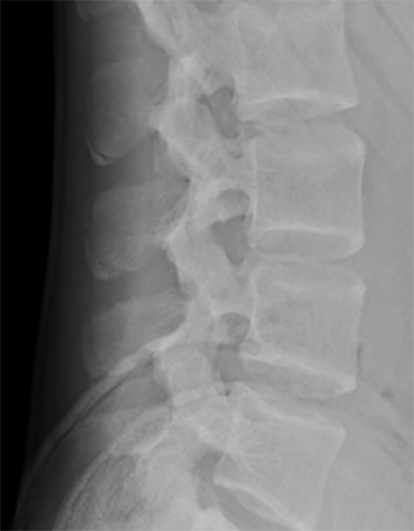

En la radiografía simple se observó esclerosis y desplazamiento del centro de osificación secundario de las apófisis espinosas L2, L3 y L4 con esclerosis del fragmento y fragmentación en L3, imágenes que recordaban a la enfermedad de Sever del calcáneo (Figura 1). Se realizó una gammagrafía con Tc99 donde se apreció hipercaptación a nivel de apófisis espinosas de L2, L3 y L4 (Figura 2) y TAC donde se confirman las lesiones (Figura 3).

Figura 1: Radiografía lateral de columna lumbar, obsérvese esclerosis y desplazamiento del centro de osificación secundario de las apófisis espinosas de L2, L3 y L4 con esclerosis del fragmento y fragmentación en L3.